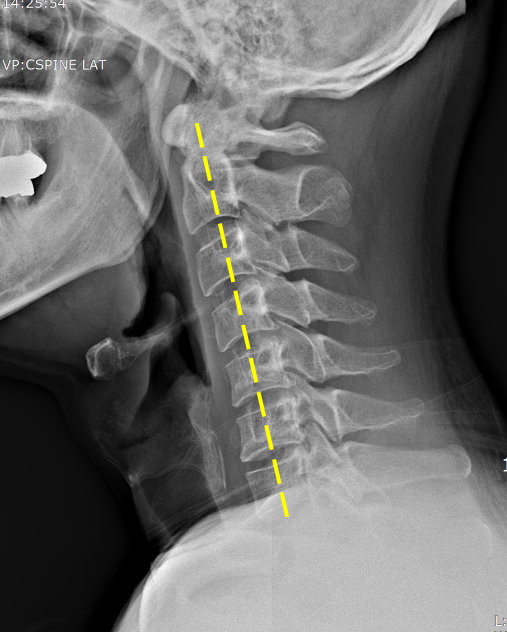

거북목 혹은 일자목 증후군은 C자 형의 커브 형태를 유지하고 있어야 할 목뼈가 일자 형태로 변형된 것을 말한다. 일자로 변형된 목은 충격 완화 능력이 떨어져 쉽게 충격을 받거나 목디스크와 같은 퇴행성질환으로 발전할 가능성도 높아진다.

일자목은 주로 컴퓨터, 스마트폰 사용자의 잘못된 자세에서 비롯되는 경우가 많은데, 긴장을 하거나 고정된 자세로 오랜 시간 작업을 하거나 휴식 없이 무리하게 컴퓨터를 사용했을 때 주로 나타난다. 또한 모니터의 위치가 눈높이보다 너무 높거나 낮은 경우, 마우스 조작 시 팔의 각도가 맞지 않거나 키보드의 방향이나 높이가 적정하지 않은 경우도 원인이 될 수 있다.